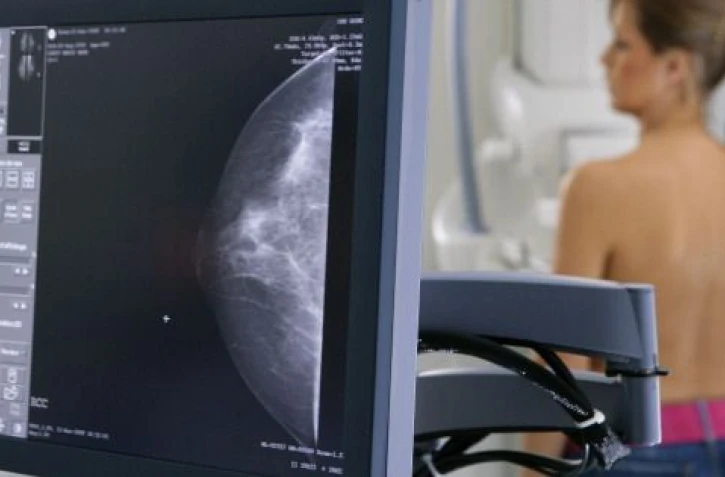

1. Dépister le cancer du sein : vous êtes une femme âgée entre 50 et 74 ans, vous êtes invitée à faire une mammographie, associée à un examen clinique tous les 2 ans.